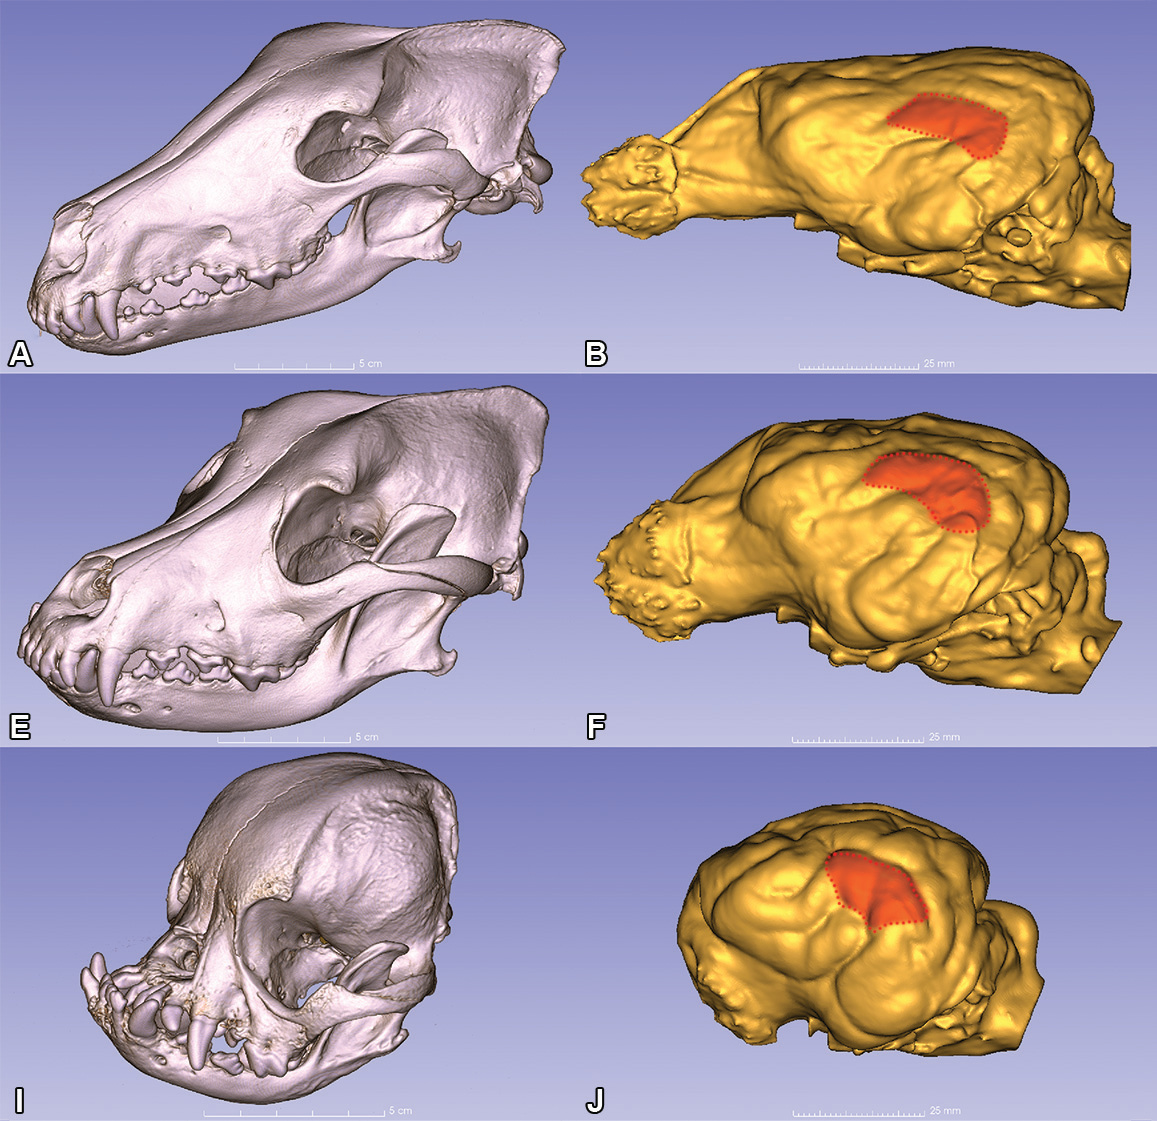

Image: Dolichocephalic (A), mesocephalic (E), and brachycephalic (I) dog skulls and their corresponding endocranial casts (brain models, B, F, J, respectively). The endocranial casts have been developed based on the digitised skulls. The middle ectosylvian auditory area is highlighted in red. Credit: Kálmán Czeibert